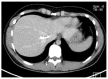

Aim: To establish a computed tomography (CT)-morphological classification for hepatic alveolar echinococcosis was the aim of the study.

Methods: The CT morphology of hepatic lesions in 228 patients with confirmed alveolar echinococcosis (AE) drawn from the Echinococcus Databank of the University Hospital of Ulm was reviewed retrospectively. For this reason, CT datasets of combined positron emission tomography (PET)-CT examinations were evaluated. The diagnosis of AE was made in patients with unequivocal seropositivity; positive histological findings following diagnostic puncture or partial resection of the liver; and/or findings typical for AE at either ultrasonography, CT, magnetic resonance imaging or PET-CT. The CT-morphological findings were grouped into the new classification scheme.

Results: Within the classification a lesion was dedicated to one out of five "primary morphologies" as well as to one out of six "patterns of calcification". "primary morphology" and "pattern of calcification" are primarily focussed on separately from each other and combined, whereas the "primary morphology" V is not further characterized by a "pattern of calcification". Based on the five primary morphologies, further descriptive sub-criteria were appended to types I-III. An analysis of the calcification pattern in relation to the primary morphology revealed the exclusive association of the central calcification with type IV primary morphology. Similarly, certain calcification patterns exhibited a clear predominance for other primary morphologies, which underscores the delimitation of the individual primary morphological types from each other. These relationships in terms of calcification patterns extend into the primary morphological sub-criteria, demonstrating the clear subordination of those criteria.

Conclusion: The proposed CT-morphological classification (EMUC-CT) is intended to facilitate the recognition and interpretation of lesions in hepatic alveolar echinococcosis. This could help to interpret different clinical courses better and shall assist in the context of scientific studies to improve the comparability of CT findings.